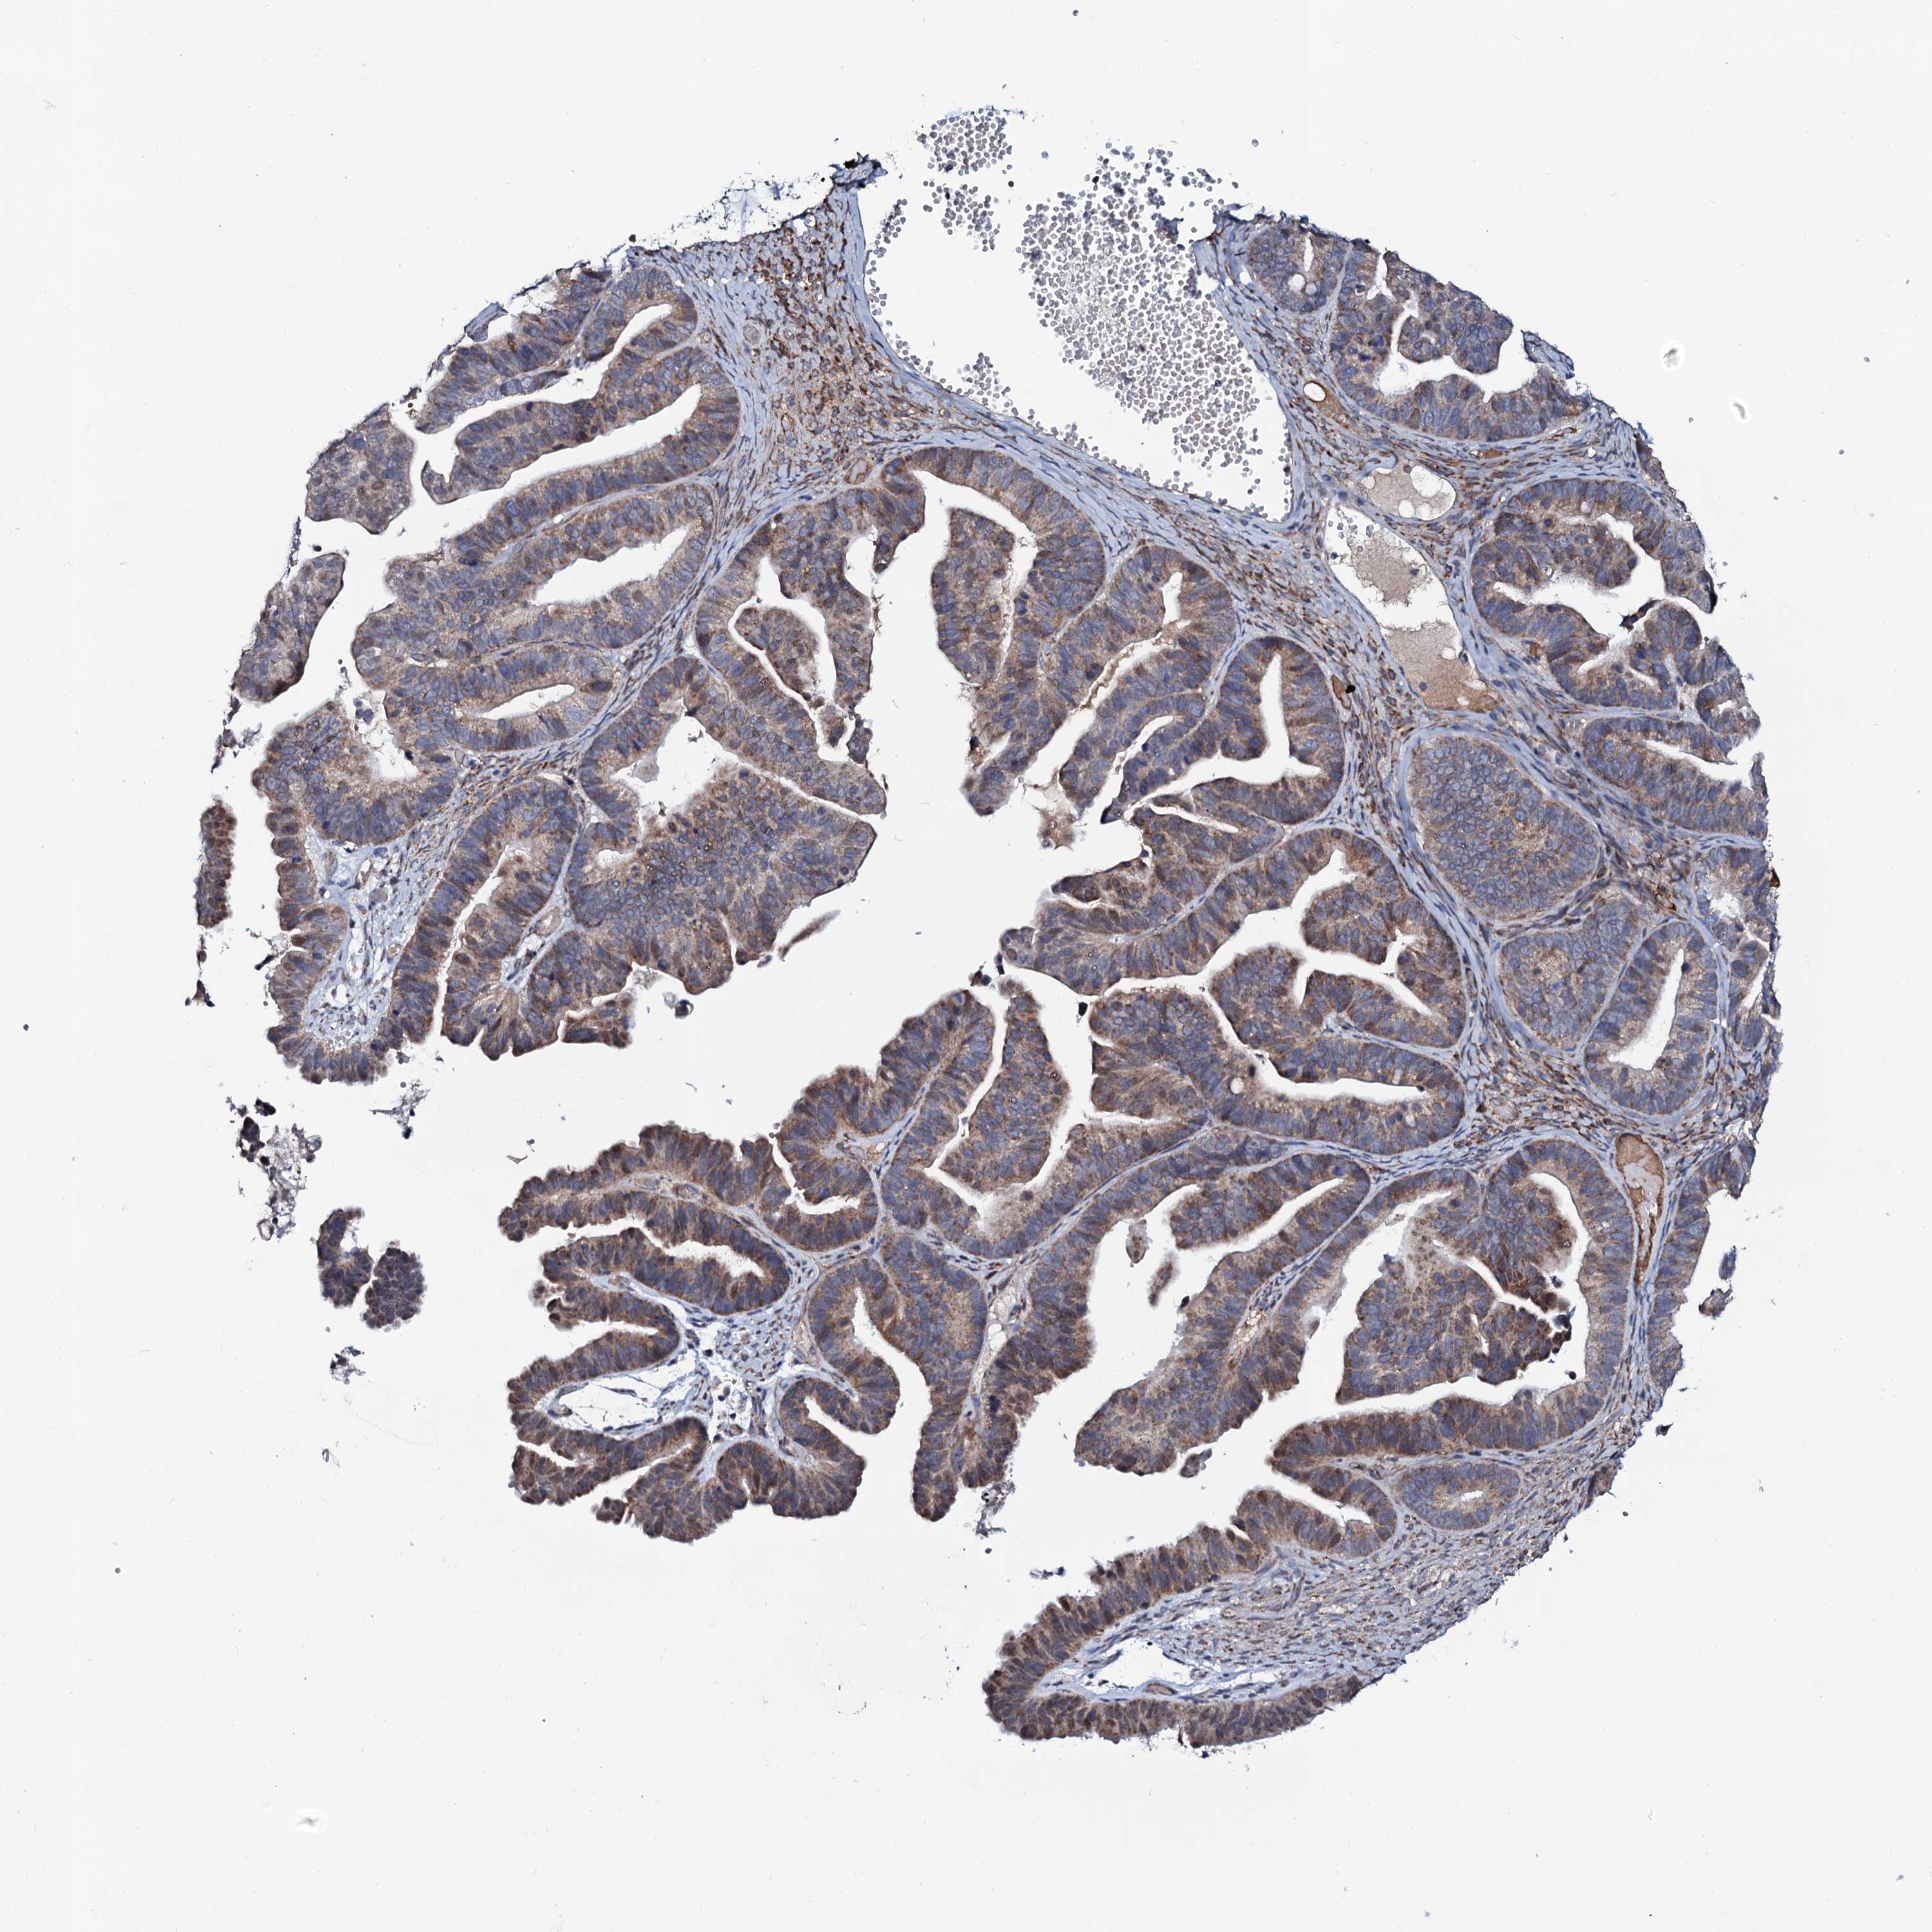

OVARIAN CANCER - Protein expressioni

A mouse-over function shows sample information and annotation data. Click on an image to view it in a full screen mode. Samples can be filtered based on level of antibody staining by selecting one or several of the following categories: high, medium, low and not detected. The assay and annotation is described here.

Note that samples used for immunohistochemistry by the Human Protein Atlas do not correspond to samples in the TCGA dataset.

Antibody stainingi

Antibody staining in the annotated cell types in the current human tissue is reported as not detected, low, medium, or high, based on conventional immunohistochemistry profiling in selected tissues. This score is based on the combination of the staining intensity and fraction of stained cells.

Each image is clickable and will lead to virtual microscopy that enables deeper exploration of all samples and also displays staining intensity scores, fraction scores and subcellular localization as well as patient and tissue information for each sample.

Antibody HPA041146

Staining

High

Medium

Low

Not detected

Intensity

Strong

Moderate

Weak

Negative

Quantity

>75%

75%-25%

<25%

None

Location

Nuclear

Cytoplasmic/membranous

Cytoplasmic/membranous,nuclear

Cystadenocarcinoma, serous, NOS

Carcinoma, endometroid

Cystadenocarcinoma, mucinous, NOS

Carcinoma, NOS